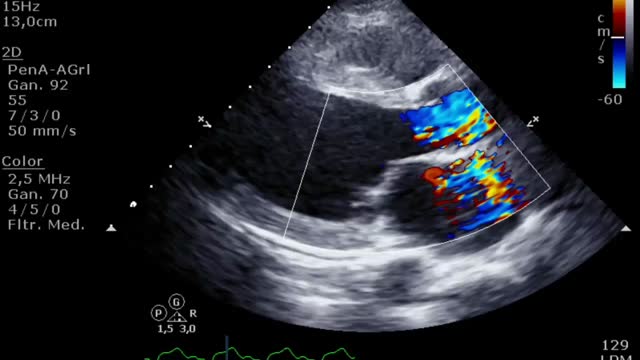

El aumento de la poscarga que condiciona la ECMO, junto con la baja contractilidad ventricular izquierda, puede comprometer la apertura valvular aórtica, pudiendo presentar un cierre precoz de la válvula (suplementario 13) e incluso permanecer cerrada (fig. 3 y suplementario 14).

El cierre aórtico es una complicación indeseada y que se debe resolver ya que, si se perpetúa, condiciona una estasis sanguínea a nivel intraventricular y un aumento de las presiones izquierdas que se traduce en una dilatación de cavidades izquierdas y, finalmente, en edema pulmonar persistente. En caso de que esto ocurra, en la ETT podremos ver humo o incluso trombos intraventriculares y signos de altas presiones (una relación E/A>2 y/o un tiempo de desaceleración del flujo mitral<150ms) izquierdas. Además de la utilidad diagnóstica/evolutiva, la ETT nos ayudará a guiar el tratamiento de esta complicación mediante la evaluación de la rentabilidad del uso/aumento del tratamiento inotrópico (suplementario 21) o guiando la implantación de dispositivos (BCIAo/Impella®) o intervencionismos (septostomía auricular, drenaje apical, ECMO veno-arterial de aurícula izquierda) para la descarga de presiones izquierdas12.